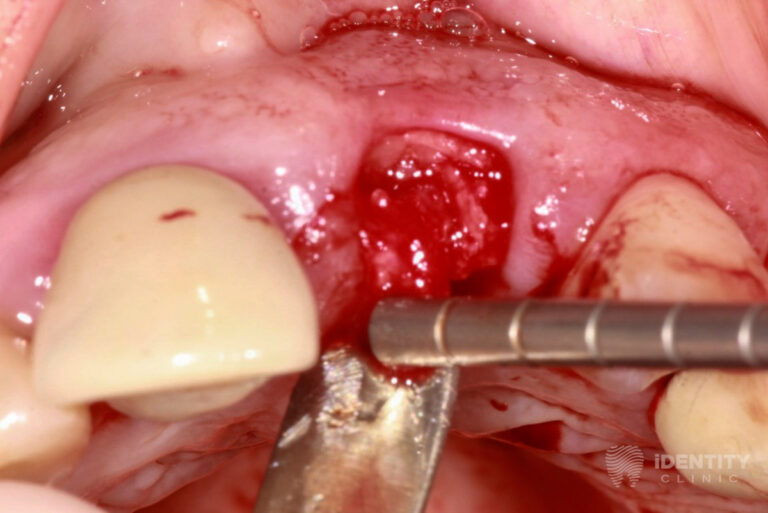

Reménytelen prognózisú 21 (bal felső első) fog eltávolítását követően a nagymértékű csonthiány miatt azonnali csontpótlást végeztünk a páciens saját csontja, illetve kötőszövete segítségével (alveolus prezerváció). Ennek 4 hónapos gyógyulási idejére az eltávolított 21 fog koronáját visszasíneztük a szomszédos fogakhoz. A teljeskörű parodontális terápiát mindeközben elvégeztük.

A bal felső első fog eltávolításával egyidőben csontpótlást (alveolus prezercációt) végeztünk. A sebészi beavatkozás lényege, hogy a fogeltávolítást követően az alveolus (az eltávolított fog helye a csontban) ne essen össze a nagymértékű csonthiány miatt, hanem azt fenntartva a páciens saját csontját és kötőszövetét felhasználva megőrizzük a csontkontúr eredeti formáját.

Mindemellett a gyógyulási idő alatt olyan mennyiségű és minőségű csont képződik az eltávolított fog helyén, melybe implantátum beültetése lehetséges.